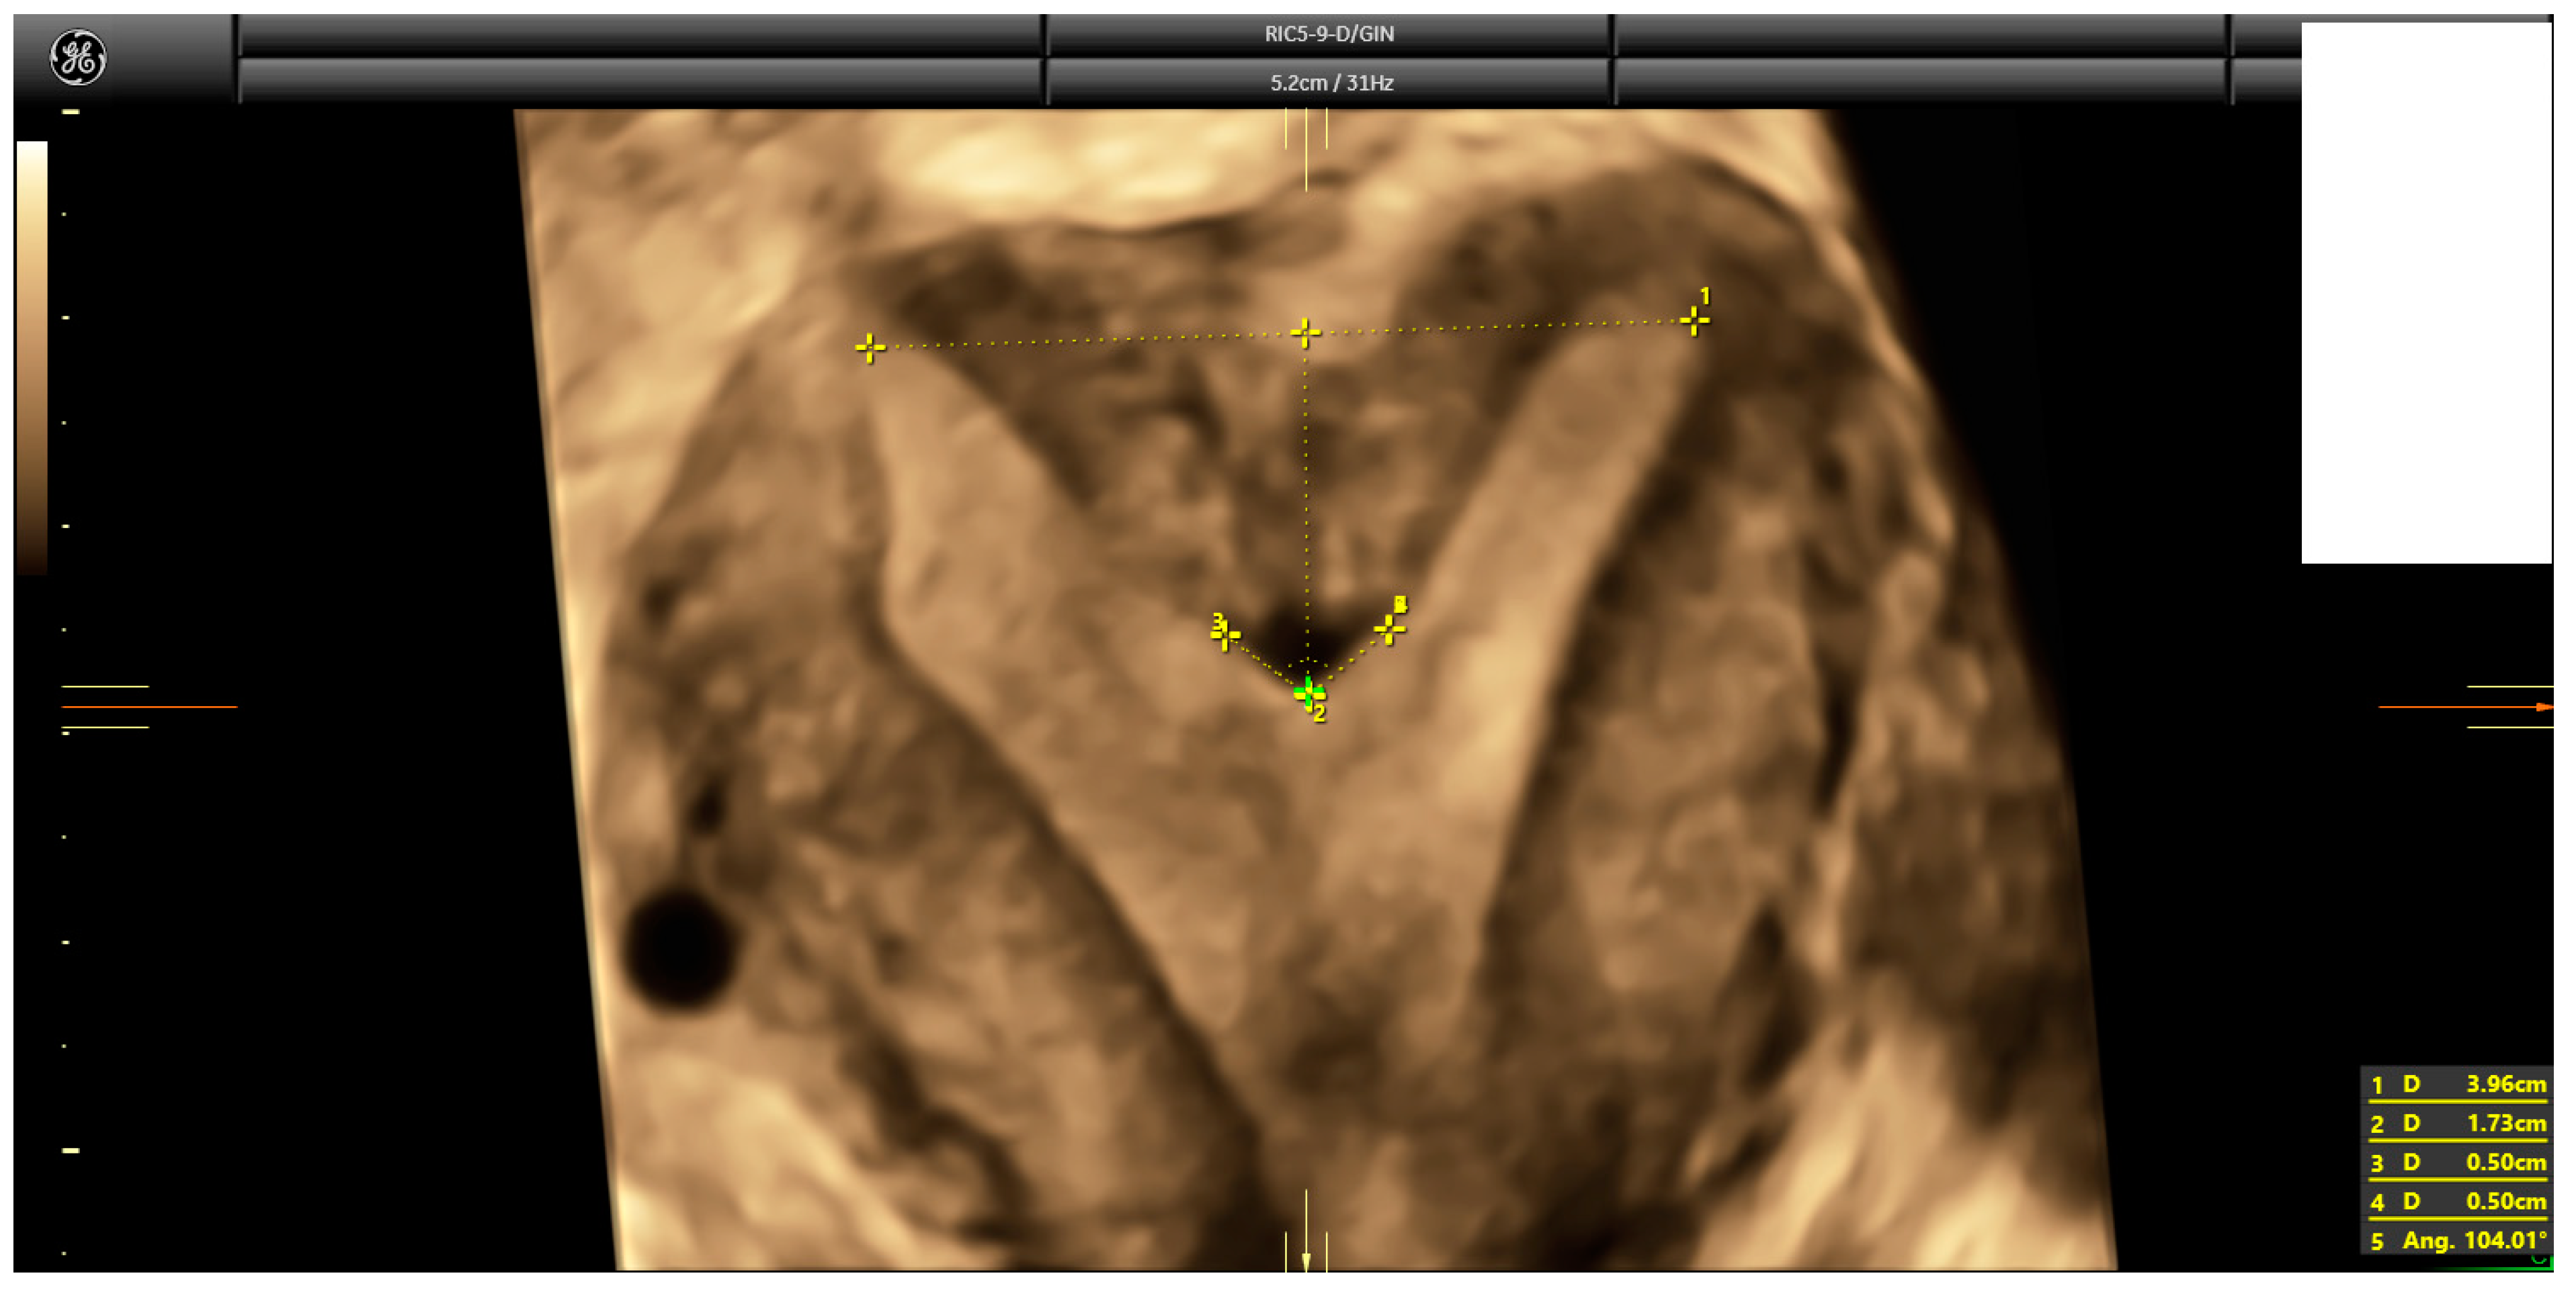

Following a comprehensive ultrasound evaluation of the uterus and adnexa, a 3D volume of the uterus was acquired according to a standardized protocol [22] for further analysis using 4DView™ software, Version 18 (GE). Subsequently, a single trained examiner (IC) conducted an offline assessment of the uterine coronal plane to measure the uterine wall thickness, fundal indentation depth, and indentation angle. Special attention was given to drawing the inter-cornual–interostial line instead of the simple interostial line and measuring the indentation angle, following the recommendations of Ludwin and Martins [23] (Figure 1).

Figure 1.

Three-dimensional ultrasound depicting how measurements were taken, according to Ludwin and Martin’s recommendations [23].

The diagnosis of a septate uterus was determined according to four different criteria (2016-ESHRE-ESGE, 2016-ASRM, 2021-ASRM, and 2019-CUME) [9,12,16] (Figure 2, Figure 3 and Figure 4). The 2016-ASRM classification defines a septate uterus as having a uterine cavity indentation depth >15 mm and an indentation angle <90° [9]. The 2021-ASRM criteria define a septate uterus as having a cavity indentation >10 mm and an indentation angle <90° [10]. The ESHRE-ESGE classification identifies a septate uterus based on an indentation-to-wall-thickness (I:WT) ratio >50% with an external fundal indentation <50% [12]. The CUME criteria specify an indentation in the fundal cavity >10 mm with an external serosal indentation <10 mm [16].

Figure 2.

A case of septate uterus according to ESHRE-ESGE criteria. I:WT ratio is 192%.